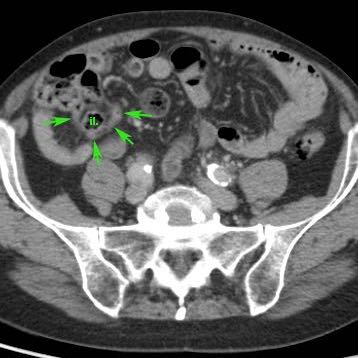

Ở bệnh nhân này với đau hố chậu phải kéo dài 18 giờ, CT chỉ cho thấy hình ảnh thâm nhiễm mỡ tối thiểu xung quanh ruột thừa 8,5 mm (mũi tên).

Siêu âm với kỹ thuật ép có kiểm soát đã cho thấy rõ ràng mô mỡ viêm tăng âm, không thể ép xẹp (đầu mũi tên) xung quanh ruột thừa.

Ở giai đoạn muộn hơn của quá trình bệnh, mô mỡ xung quanh ruột thừa có xu hướng tăng thể tích.

Đây là mạc nối mỡ đã di chuyển về phía ruột thừa trong nỗ lực bao bọc tình trạng thủng sắp xảy ra.